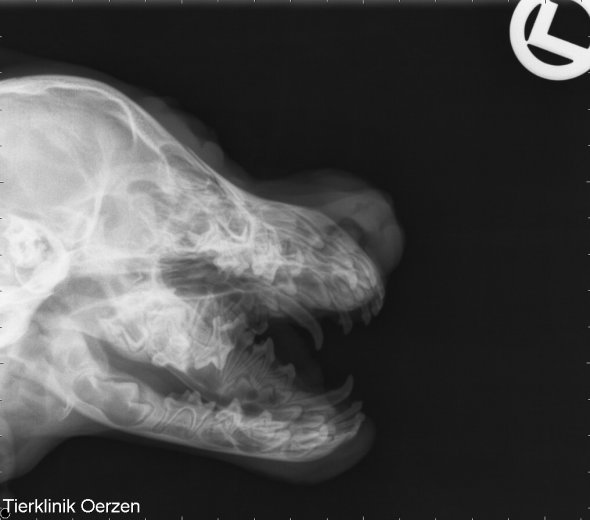

Hier setzte ich mal ein digitales Röntgenbild von Lesley`s Zähnen rein.

Ich finde es schon enorm wie man die bleibenden Zähne sehen kann.

Ich würde sagen, dass P1 fehlt . Kann das sein?

Ist schwer zu erkennen, sehe ich auch so. Ist mehr geraten als sonstwas!

auf der CD sind insgesamt 8 Bilder des Kiefers in allen möglichen Stellungen, Winkeln und mit mehr oder weniger geöffnetem Fang.

Hast Recht, 1 P1 soll fehlen, bzw. ist nicht zu erkennen, wobei Geli gesagt wurde, dass eben der P1 schwierig ist zu deuten, kann also höchstwahrscheinlich so sein, dass der eine auch noch kommt.

Die Bilder sind gesichert diagnostiziert und in der Klinik kann man sogra die Zahnwuchsrichtung deuten und eine Prognose erstellen und das BESTE ohne Narkose.